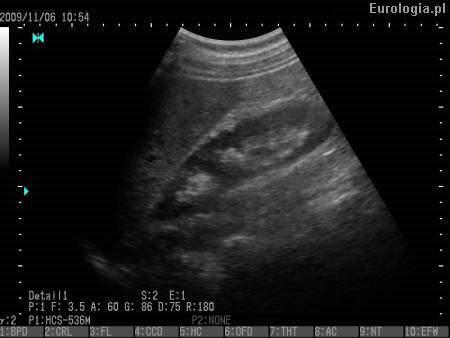

USG układu moczowego

Fot. Nerka prawa - obraz USG.